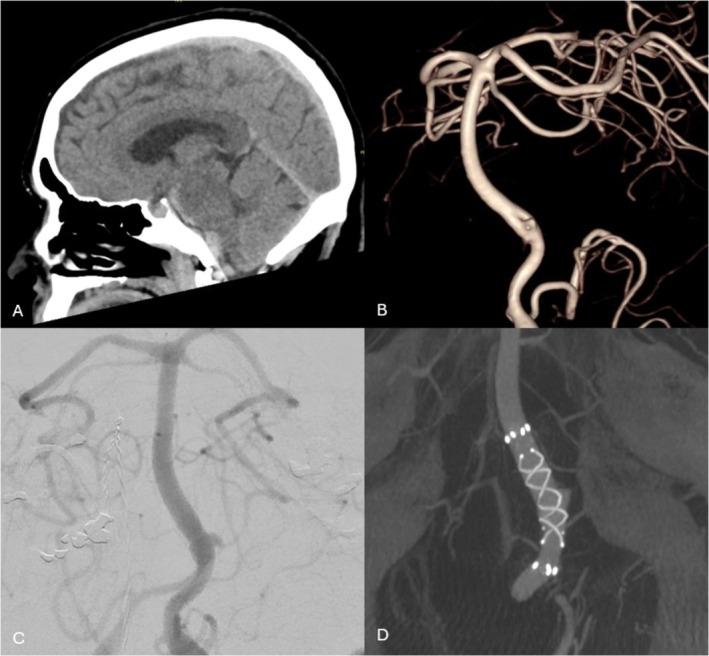

A total of 39 consecutive patients (21% presenting with acute rupture) with 52 aneurysms treated with 40 FRED X devices between June 2021 and September 2024 were included in this study. Aneurysms were predominantly saccular (88%) and located in the ICA (82%), with a median size of 5.1 mm (IQR 2.4-8). Satisfactory wall apposition was achieved in 98% of cases. Additional coiling was performed in 20%, and balloon angioplasty in 5%. At a median follow-up of 28 weeks, complete aneurysm occlusion was achieved in 74% of cases, with adequate occlusion (> 90%) in 86%. Minor adverse events occurred in 10% and major adverse events in 5%. Overall mortality was 5%, exclusively in acute subarachnoid haemorrhage cases.

本研究纳入了2021年6月至2024年9月期间连续39例患者(21%为急性破裂),共52个动脉瘤,使用了40个FRED X装置进行治疗。动脉瘤主要为囊状(88%),位于颈内动脉(82%),中位大小为5.1毫米(四分位间距2.4 - 8)。98%的病例实现了满意的壁贴合。20%的病例进行了额外的弹簧圈栓塞,5%的病例进行了球囊血管成形术。中位随访28周时,74%的病例实现了动脉瘤完全闭塞,86%的病例实现了充分闭塞(>90%)。10%的患者发生了轻微不良事件,5%的患者发生了严重不良事件。总体死亡率为5%,仅发生在急性蛛网膜下腔出血病例中。